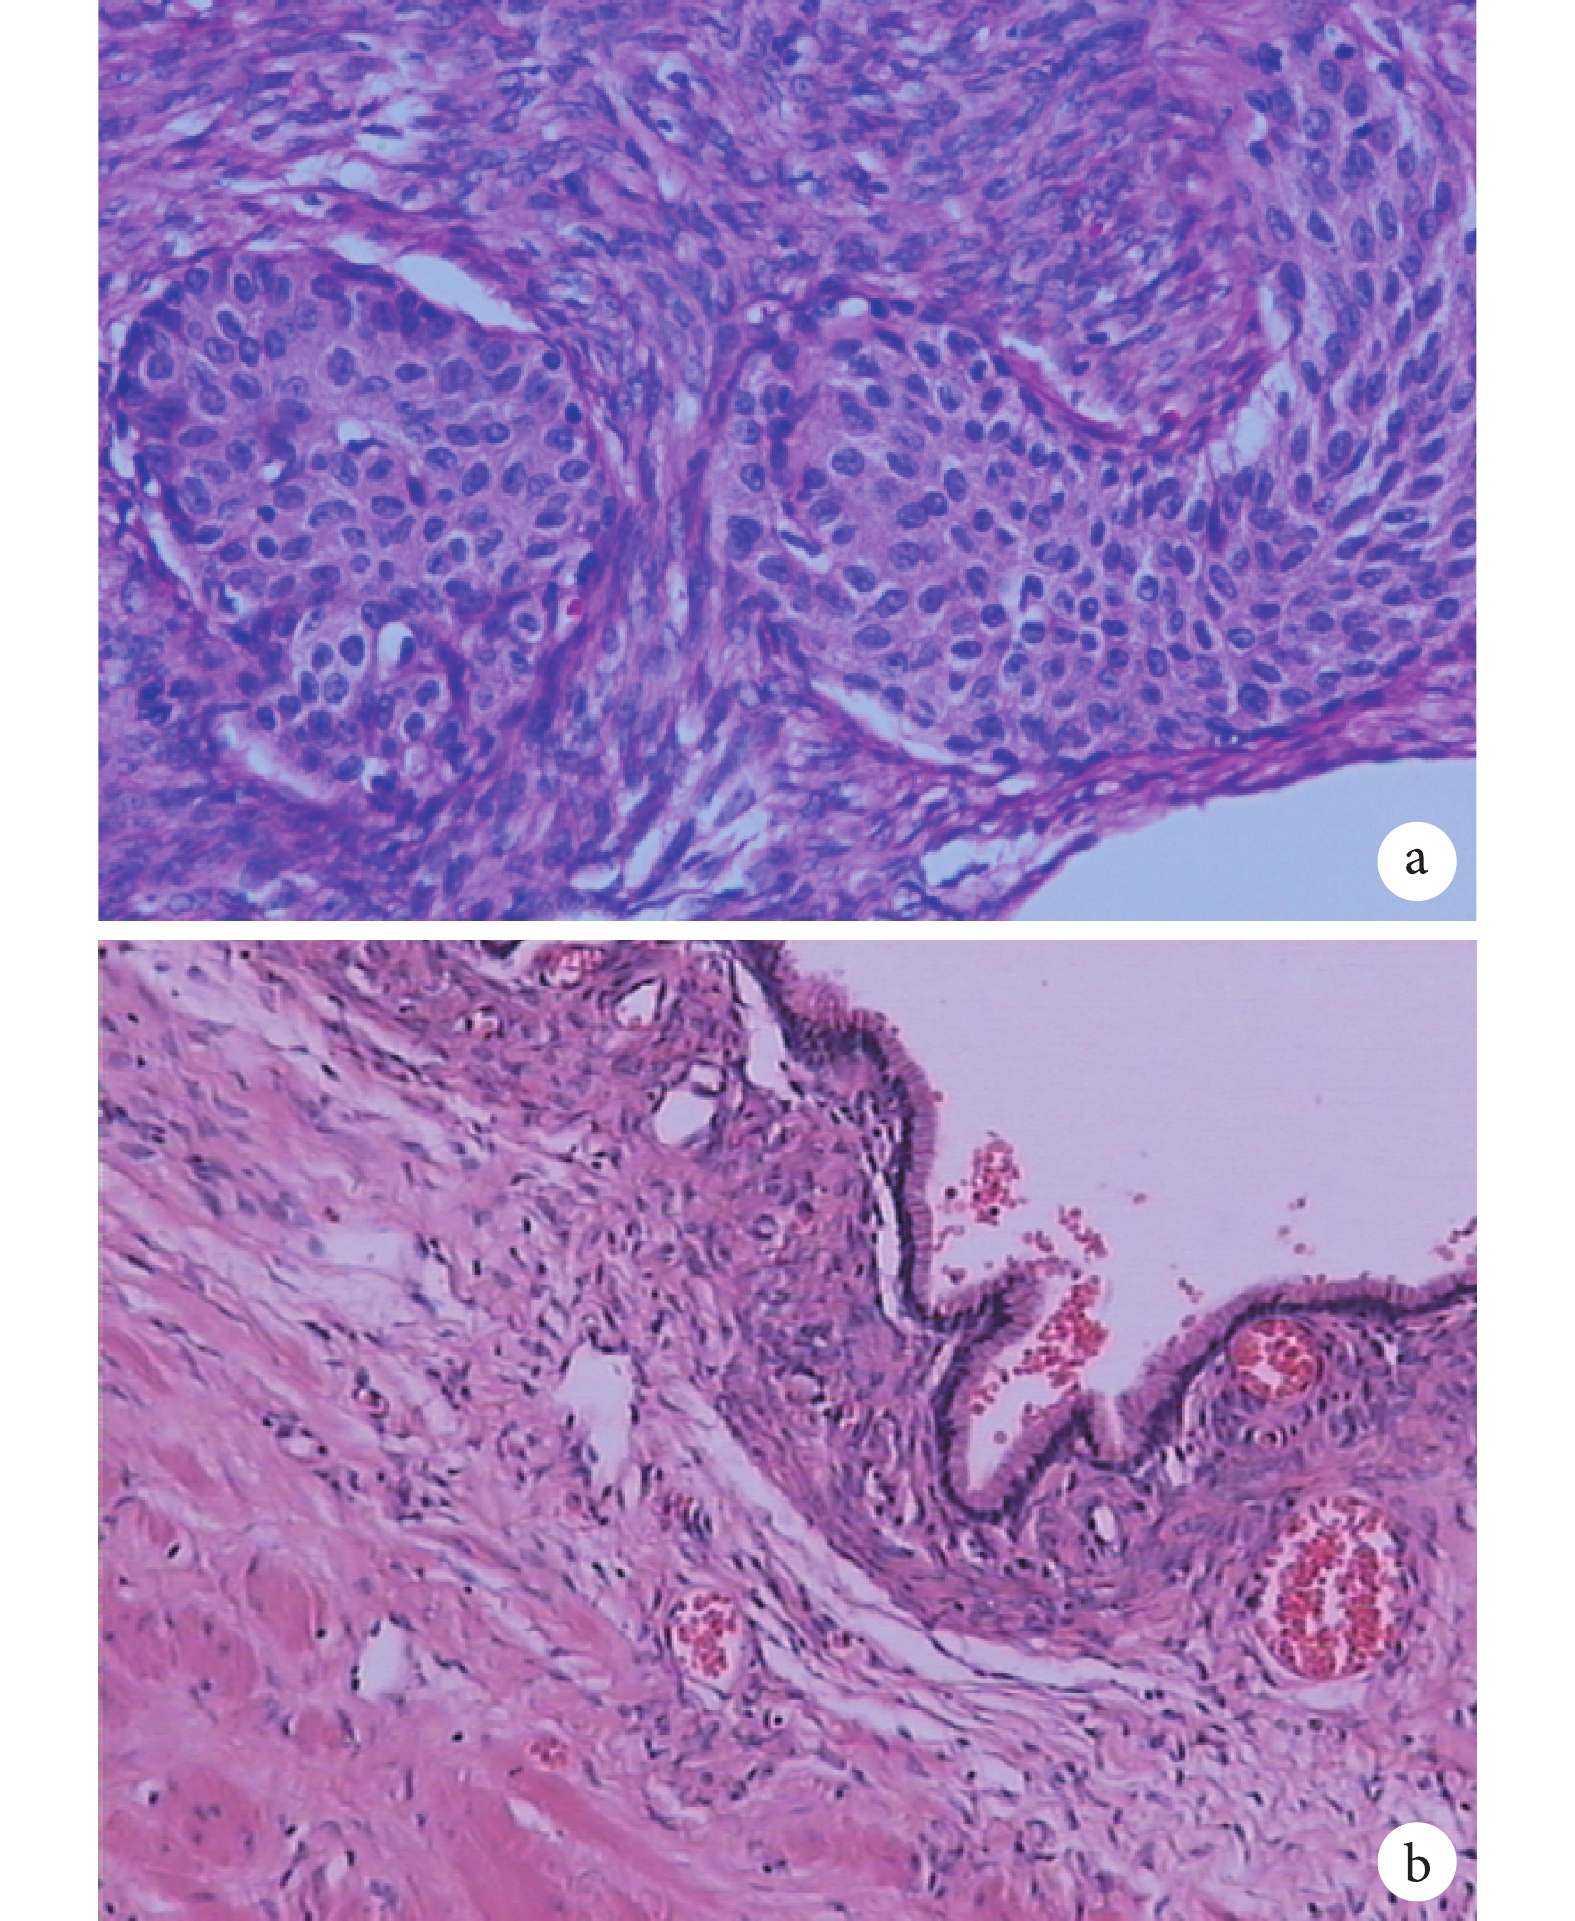

a. 腫瘤由類似于尿路上皮的實性上皮細胞巢和纖維組織構成(蘇木精-伊紅染色 ×20);b. 囊壁內襯單層黏液柱狀上皮(蘇木精-伊紅染色 ×10)